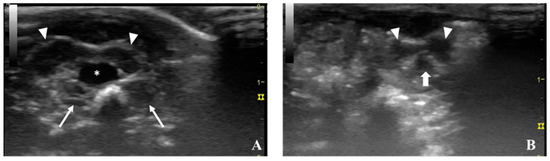

5.1. Ultrasonography